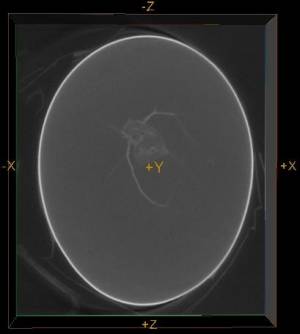

Figure 3. Left and right sagittal CT images of mouse with iodinated liposome injected in left eye vein

Figure 4. Transverse CT image of mouse